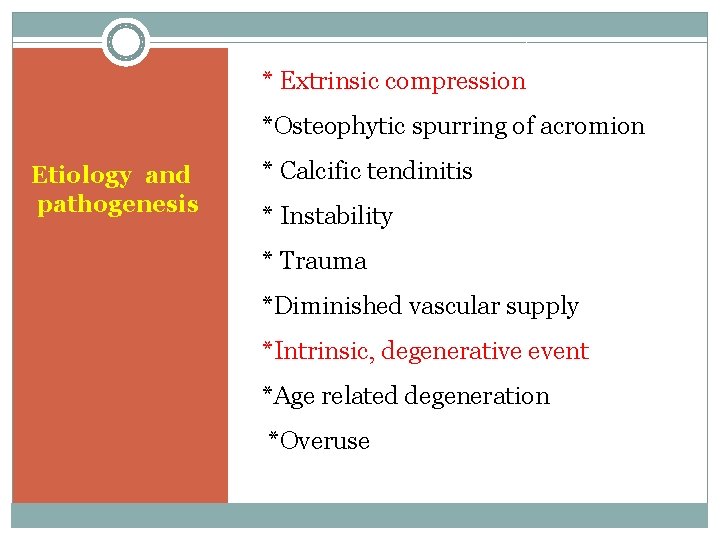

* Extrinsic compression *Osteophytic spurring of acromion Etiology and pathogenesis * Calcific tendinitis * Instability * Trauma *Diminished vascular supply *Intrinsic, degenerative event *Age related degeneration *Overuse